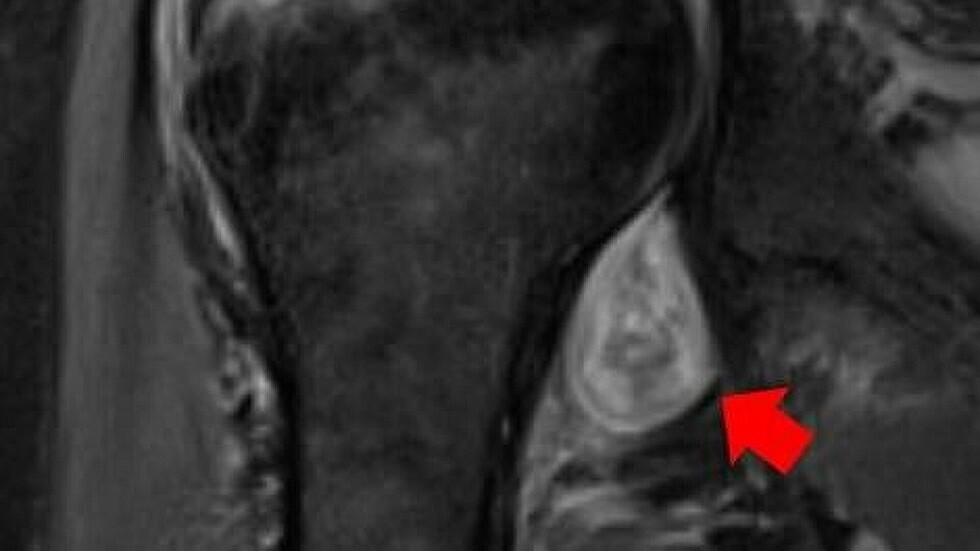

واستخدم الباحثون في فحص هؤلاء المرضى التصوير المقطعي بالكمبيوتر، والتصوير بالرنين المغناطيسي والموجات فوق الصوتية، ووجدوا أن الأعراض "الغريبة" بعد المرض، مرتبطة برد فعل المناعة الذاتية للجسم.

ويضيف ديشموخ، من أجل تشخيص أكثر دقة يجب استخدام طرق التصوير الحديثة، ويقول، "تسمح لنا الصور، بتمييز الألم البسيط في الجسم الذي يلاحظ في  حالة الإصابة بالإنفلونزا ، عن ألم العضلات والمفاصل الناتج عن الإصابة بمرض "كوفيد-19". حتى أن الخبراء يمكنهم في بعض الحالات استنادا إلى هذه الصور تشخيص إصابة الشخص بـ "كوفيد-19" إذا لم تظهر عليه أعراض المرض ولم يشعر بإصابته".

ويشير الباحثون، إلى أن الطرق الشعاعية، تسمح باكتشاف مختلف التكوينات: الوذمة، تغيرات التهابية في النسجة، وجود السوائل والأورام، والأورام الدموية، والأنسجة الميتة التي تشير إلى بداية الغنغرينا.